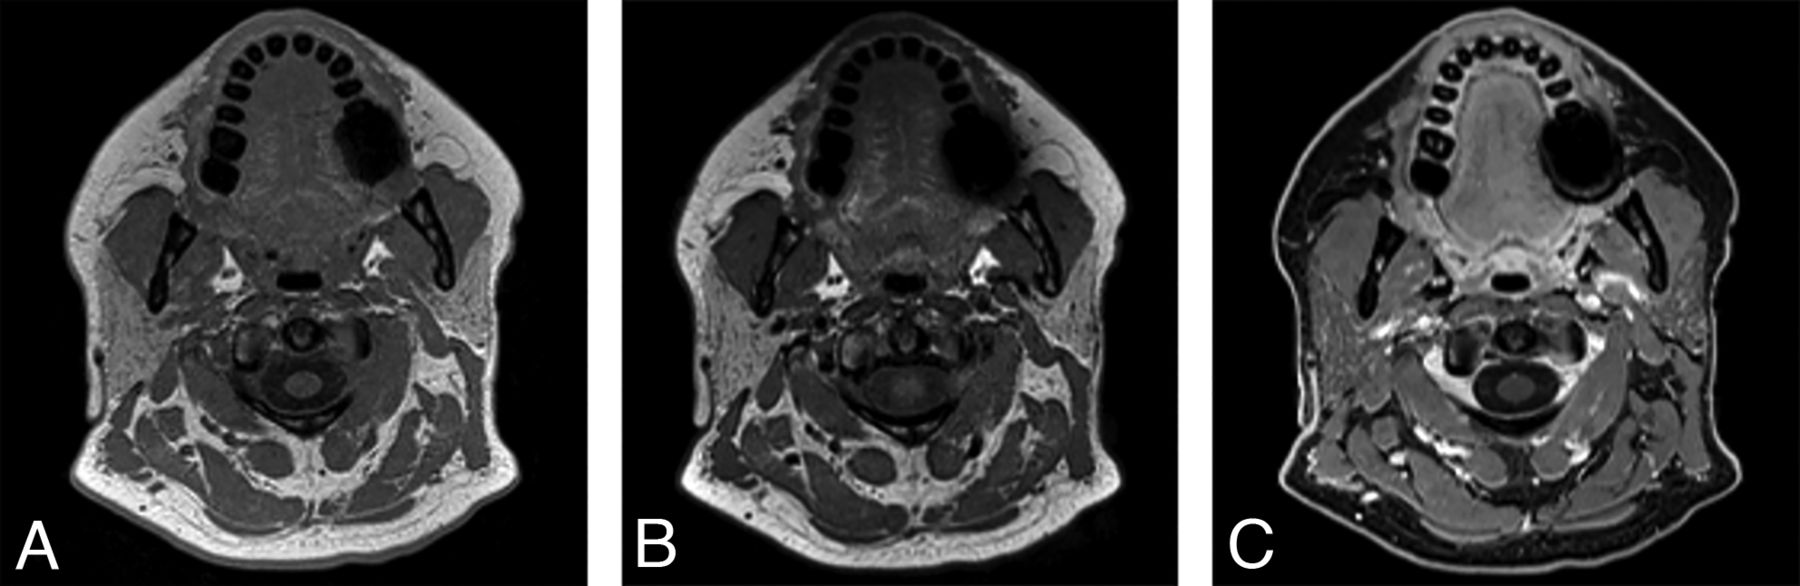

Our 1.5T protocol was adapted from the 3T protocol to provide the same resolution; 1.5T protocol parameters are provided in the Online Supplemental Data alongside the 3T protocol parameters. An example is provided in Fig 3, images from a 27-year-old man with a right supraclavicular and chest wall desmoid tumor.

A 27-year-old man with right supraclavicular and chest wall desmoid tumor images on a 1.5T Magnetom Aera system (Siemens). The tumor (arrows) is shown on a general neck protocol, 1.0-mm isotropic sagittal acquisition T1 SPACE axial reformat (A) and T1 VIBE Dixon (B) postcontrast axial reformatted images. Image quality and fat suppression remain good at the level of the thoracic inlet. In addition, T1 SPACE axial reformat (C) and T1 VIBE Dixon (D) postcontrast axial reformat images through the face are provided to show image quality in that region.